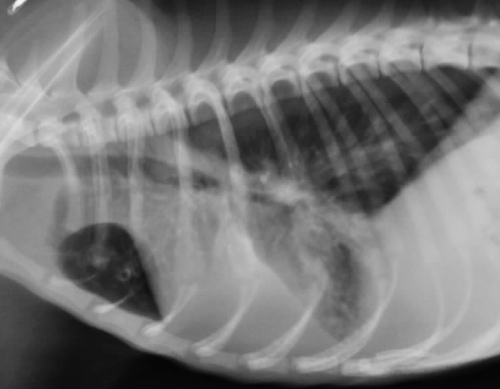

左下が胸部レントゲン写真で、寄生虫性の肺炎、気管支炎を示しております。写真のワンちゃんは生後1年弱、糞線虫が治療されていませんでした。右下の写真は正常レントゲン写真です。